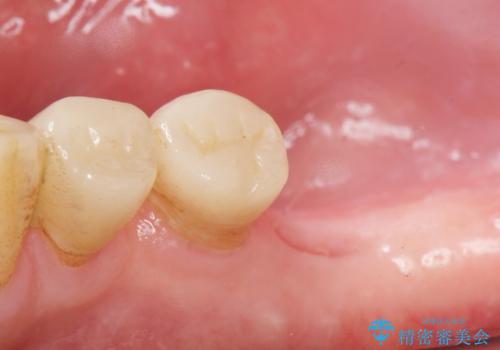

奥歯でしっかりと咬むことができるようになり、大変喜んで頂けました。

クラウンの種類:オールセラミッククラウン スタンダード